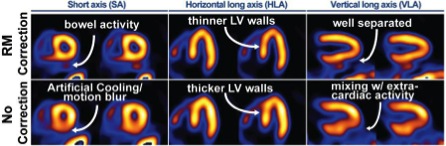

One example of the research accomplishments of the laboratory is our work on the detection and compensation of patient motion during the up to 16 minute period which the patient is required to remain motionless for nuclear medicine studies. We have taken the approach of combining estimates of patient motion as determined from the nuclear medicine images themselves with information from our visual-tracking system (VTS) which tracks the motion of retro-reflective markers on stretchy bands wrapped about the patient to provide a combined correction of respiratory and bodily motion. Once motion is determined it is corrected by inclusion in iterative reconstruction as illustrated in the following figure. These investigations are funded by NIH grant R01-HL122484.

Clinical SPECT images showing benefits of respiratory motion correction (RM) as noted in top row versus second row which is without RM correction.